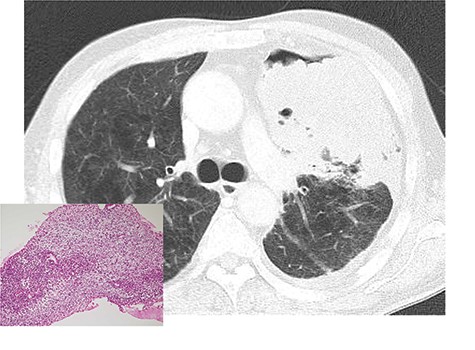

A 64-year-old male with a 92-pack/year smoking history was admitted to the emergency department of the institution with sudden shortness of breath. Chest X-ray and computed tomography on admission revealed the presence of massive left pleural effusion and a large tumor (diameter: 13 cm) occupying the patient’s left thoracic cavity (Fig. 1). Pleural effusion cytology and a bronchofiberscopic study failed to show any evidence of disease. Under local anesthesia, percutaneous needle biopsy performed through the left thoracic wall revealed the presence of a sarcomatous lesion (Fig. 1) and positive immunohistochemical staining for CD56 and desmin. Based on these findings, the diagnosis of MTT was considered. There was no evidence of distant metastases.

Chest computed tomography after tube thoracostomy. A large tumor with irregular margins occupied the left thoracic cavity. Percutaneous needle biopsy showed a malignant sarcomatoid neoplasm, which was suggestive of malignant triton tumor (left bottom).